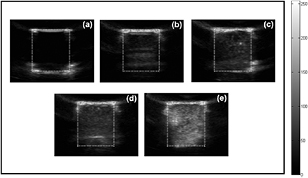

Standard image High-resolution image3.5. In vitro US phantom imaging

Moreover, US imaging was carried out for the gel phantom in the testing chamber to investigate the impact of the integration of SPIOs on the acoustic scattering capability of SPIO-albumin MBs, which is a dominant factor for their performance in US imaging. To provide significant and distinguishable ultrasound contrast enhancement effect, the MB samples in each group were diluted 30 times and then injected into the testing chamber. Typical US images captured for degassed water and MB solutions with varied SPIO concentrations are shown in figure 6. Compared to degassed water (figure 6(a)), hyperechoic regions can be clearly observed in the testing chamber by adding MB solutions with higher SPIO concentration (figures 6(b)–6(e)). For each sample, the gray-scale image intensity is calculated in the region of interest (ROI) using MATLAB software. The contrast-to-tissue ratio (CTR) is estimated as the ratio of averaged gray-scale intensities between MB and tissue (phantom) regions. According to five repeated measurements, the averaged CTR values are calculated to be −0.59 ± 0.001, 5.89 ± 0.70, 8.97 ± 0.80, 11.04 ± 0.72 and 12.844 ± 0.56 dB for the samples of degassed water and Group 1 to 4, respectively. A negative CTR is discerned for degassed water, which indicates that the tissue-mimicking phantom has stronger echo response than the water. By adding albumin-shelled MBs without SPIOs, significant contrast enhancement effect is achieved. It is noteworthy that, as the effective concentration of SPIOs loaded to MBs increases from 0 to 292.0 μg ml−1, the corresponding CTR is further improved, which suggests that greater US echo intensity can be contributed by MBs integrated with more SPIOs. This will be discussed in detail in the section of discussion.

Figure 6. In vitro US images of (a) degassed water; (b) albumin-shelled MBs; and SPIO-albumin MBs with varied SPIO concentrations of 19.6 (c), 114.7 (d) and 292.0 (e) μg ml−1. The white dotted box indicates the ROI in each image and the gray scale bar represents the dynamic range used in the images.

Download figure:

Standard image High-resolution image3.6. US-facilitated VEGF165 transfection assessments for SPIO-albumin microbubbles

Aiming at dual-modality imaging contrast agents, the acoustic scattering properties of SPIO-albumin MBs was examined based on in vitro US imaging. The results shown in figure 6 demonstrate that, with more SPIOs integrated in MB shells, the contrast-to-tissue ratio could be improved by about 13 dB. For MBs coated with thin shell materials (i.e. shell thickness is much smaller than bubble radius), their dynamic behaviors can be described by Rayleigh-Plesset (RP)-like equations (Hoff et al 2000). The MB scattering cross section (σs), which represents the scattering property of MBs, is calculated as ![${{\sigma}_{s}}=4\pi R{{_{0}^{2}}^{{{\Omega}^{4}}}}\left/\left[{{\left({{\Omega}^{2}}-1\right)}^{2}}+{{\Omega}^{2}}{{\delta}^{2}}\right]\right.$](https://content.cld.iop.org/journals/0031-9155/59/22/6729/revision1/pmb501882ieqn001.gif) (Church 1995, Hoff et al 2000), with

(Church 1995, Hoff et al 2000), with  and

and ![${{\omega}_{0}}=\sqrt{\left[3\gamma {{P}_{0}}+12{}^{{{G}_{s}}{{d}_{s}}}\left/{}_{{R}_{0}}\right.\right]/{{\rho}_{L}}R_{0}^{2}}$](https://content.cld.iop.org/journals/0031-9155/59/22/6729/revision1/pmb501882ieqn003.gif) . Here, R0 is the MB ambient radius; δ is the damping coefficient; γ is the polytropic exponent of the gas; P0 is the hydrostatic pressure in the surrounding liquid; ds is the shell thickness; Gs is the shell shear modulus; ω is the angular frequency of driving signal and ω0 is the linear resonance angular frequency. Figure 3 illustrates that the mean value of MB diameter rises with the increasingly effective SPIO concentration integrated in MBs. According to the above formulas, the increase in R0 would lower the MB resonance frequency ω0 and in turn, enlarge its scattering cross section, which provides theoretical proof for the experimental observations on the enhanced CTR in US images.

. Here, R0 is the MB ambient radius; δ is the damping coefficient; γ is the polytropic exponent of the gas; P0 is the hydrostatic pressure in the surrounding liquid; ds is the shell thickness; Gs is the shell shear modulus; ω is the angular frequency of driving signal and ω0 is the linear resonance angular frequency. Figure 3 illustrates that the mean value of MB diameter rises with the increasingly effective SPIO concentration integrated in MBs. According to the above formulas, the increase in R0 would lower the MB resonance frequency ω0 and in turn, enlarge its scattering cross section, which provides theoretical proof for the experimental observations on the enhanced CTR in US images.

The MRI (figure 5) and US imaging (figure 6) studies have confirmed that, with facile surface modification, the presence of Fe3O4 in MB shell provides enough acoustic and magnetic susceptibility to albumin-shelled UCA MBs to accomplish superb US and MR detectability and sensitivity. To target at multifunctional imaging and drug delivery agents, the therapeutic capability of SPIO-albumin MBs on VEGF165 transfection was also examined in the present work. PEI:VEGF165 complexes were used in this work instead of naked DNA because PEI has been shown to be a relatively efficient non-viral vector and because the synergistic effect of US and PEI on DNA transfection has also been reported in previous work (Deshpande and Prausnitz 2007, Qiu et al 2010, Zhang et al 2013). As reported, US-induced IC activities, which could be dramatically enhanced by the addition of UCA MBs, can transiently enhance cell membrane permeability through sonoporation processes to facilitate the entry of foreign gene/drugs into cells. In order to achieve a better understanding of the mechanisms involved in SPIO-albumin- MB-medicated VEGF165 transfection induced by US exposures, the 'amount' of IC energy cumulated over the US exposure duration (i.e. ICD), cell viability after treatments and effective VEGF165 transfection efficiency were all systemically assessed here at varied p- and SPIO concentration in MB solutions.